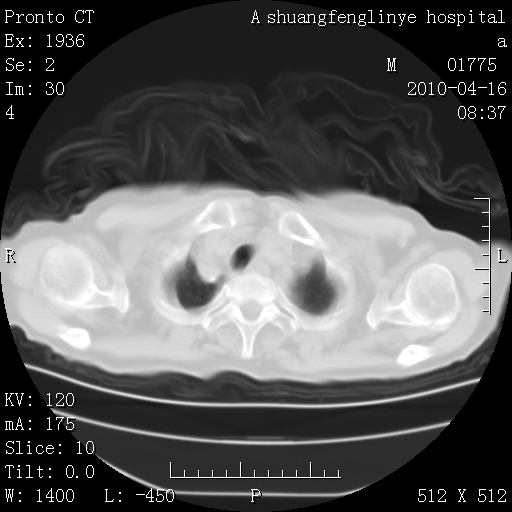

标题: CT25784:咳痰、请会诊!结核? [打印本页]

标题: CT25784:咳痰、请会诊!结核?

考虑左肺上叶增殖灶、纤维灶。

老年肺间质纤维化,肺动脉高压-----肺心病。

慢支肺气肿,左上陈旧性结核,主动脉冠脉钙化

1)左肺上叶结核(纤维、增殖病灶)。2)冠状动脉及主动脉钙化。

1)左肺上叶结核(纤维、增殖病灶)。2)冠状动脉及主动脉钙化。肺动脉高压